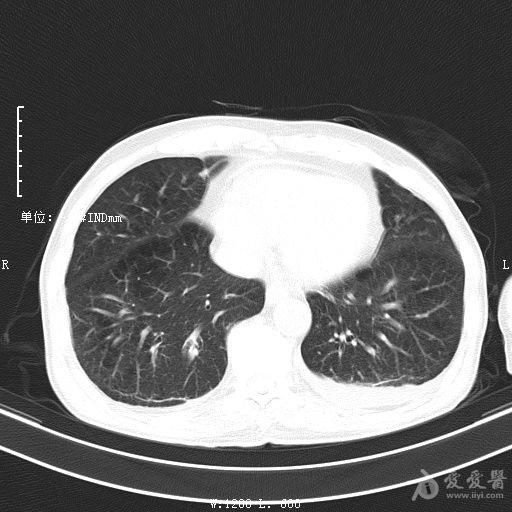

最新的肺炎疫情形勢嚴(yán)峻,病毒變異使得防控工作更加復(fù)雜,許多地方出現(xiàn)了新的病例,甚至有些地區(qū)的疫情出現(xiàn)了反彈,這不僅是對醫(yī)療系統(tǒng)的考驗(yàn),更是對每一個生命的考驗(yàn),我們需要密切關(guān)注疫情動態(tài),共同應(yīng)對這場挑戰(zhàn)。??